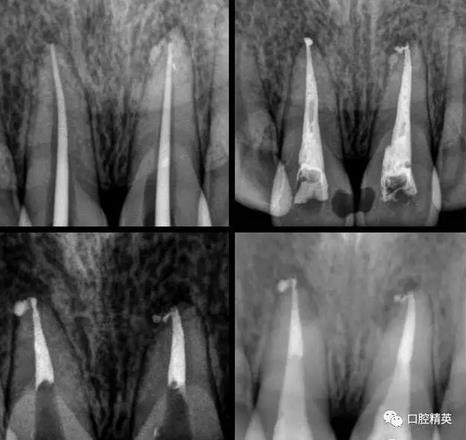

處理:(初診)取原始模型,11,21開髓,拔髓,擴根,沖洗,CP碘仿棉捻開放。

(二診)取出開放物,雙氧水沖洗,氫氧化鈣糊劑加碘仿暫封2周。

(三診) 去除暫封物及糊劑,鹽水沖洗,隔濕,干燥,大錐度牙膠尖配合樹脂根充糊劑行根管充填,一周后復診。

(四診)11,21唇側(cè)膿腫基本消除,叩(-),預備樁道,置入纖維樁,備牙,取模,翻制臨時冠。

術中根管治療,置人纖維樁,牙體預備,臨時冠修復